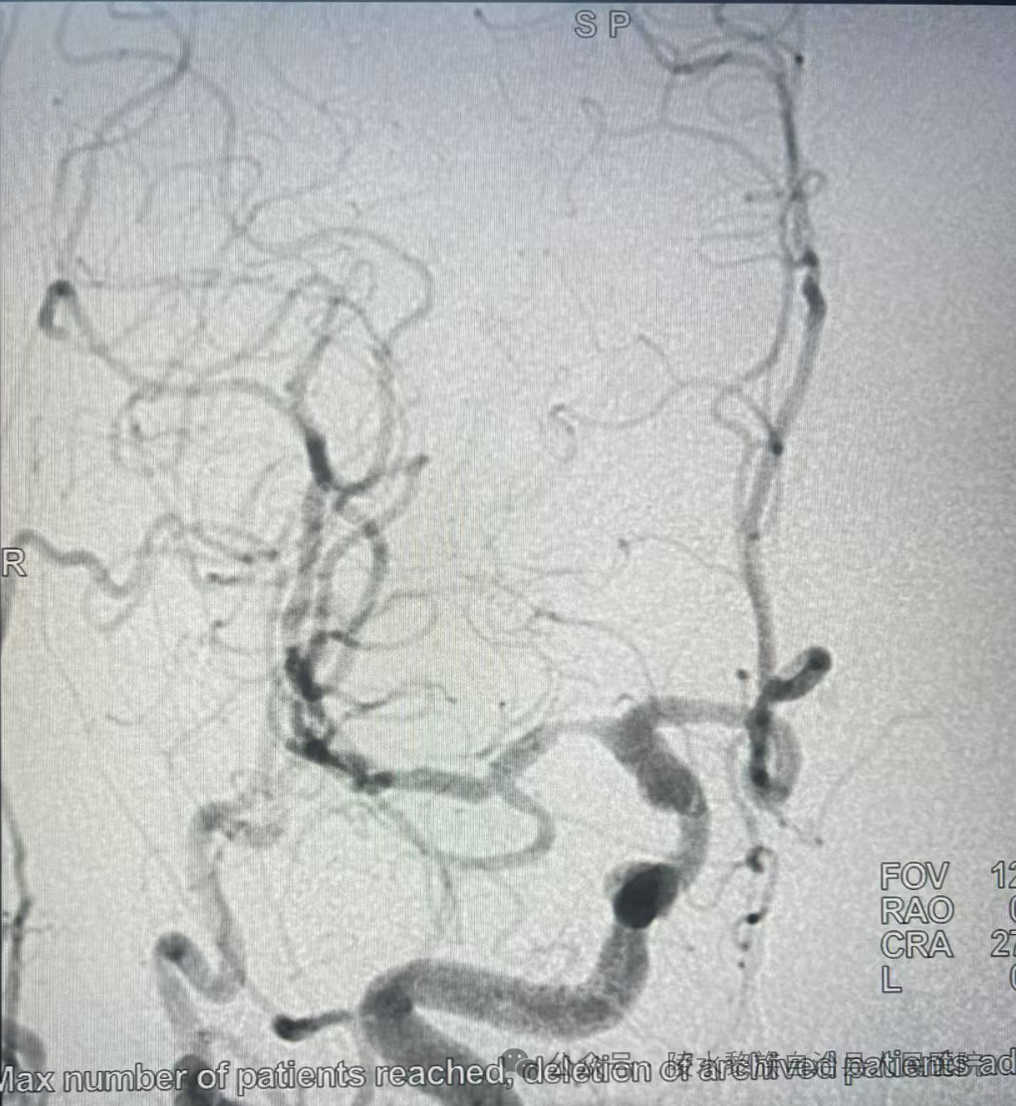

经远桡动脉穿刺全脑血管造影术是一种通过手腕远端的桡动脉进行穿刺,将导管送至脑血管,注入造影剂并拍摄影像的检查方法。它利用桡动脉作为入路,避免了传统经股动脉穿刺对下肢动脉的损伤,同时减少了术后卧床时间和并发症风险。

这项技术不仅适用于脑血管疾病的诊断,还可以在检查过程中直接进行介入治疗,如血管成形术、动脉瘤栓塞术等,实现了诊断与治疗的一体化。

2. 脑动脉瘤的介入治疗:通过远桡动脉入路,医生可以精确地将微导管送至动脉瘤部位,进行栓塞治疗,降低动脉瘤破裂的风险。

3. 脑血管畸形的评估与治疗:这项技术可以清晰显示畸形的供血动脉和引流静脉,为手术或介入治疗提供重要参考。